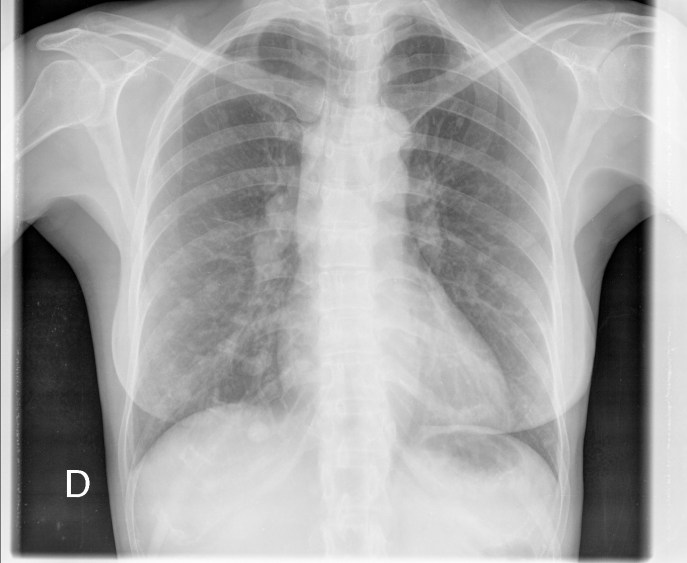

CASO: Revisión.

Hallazgos:

- Mastectomía derecha.

- Resto del estudio sin hallazgos de significación.

RECUERDA LA SISTEMÁTICA PARA NO OLVIDAR NINGUN HALLAZGO. A esta paciente le han extirpado la mama derecha, motivo por el cual se observa una asimetria entre las densidades de las bases pulmonares.